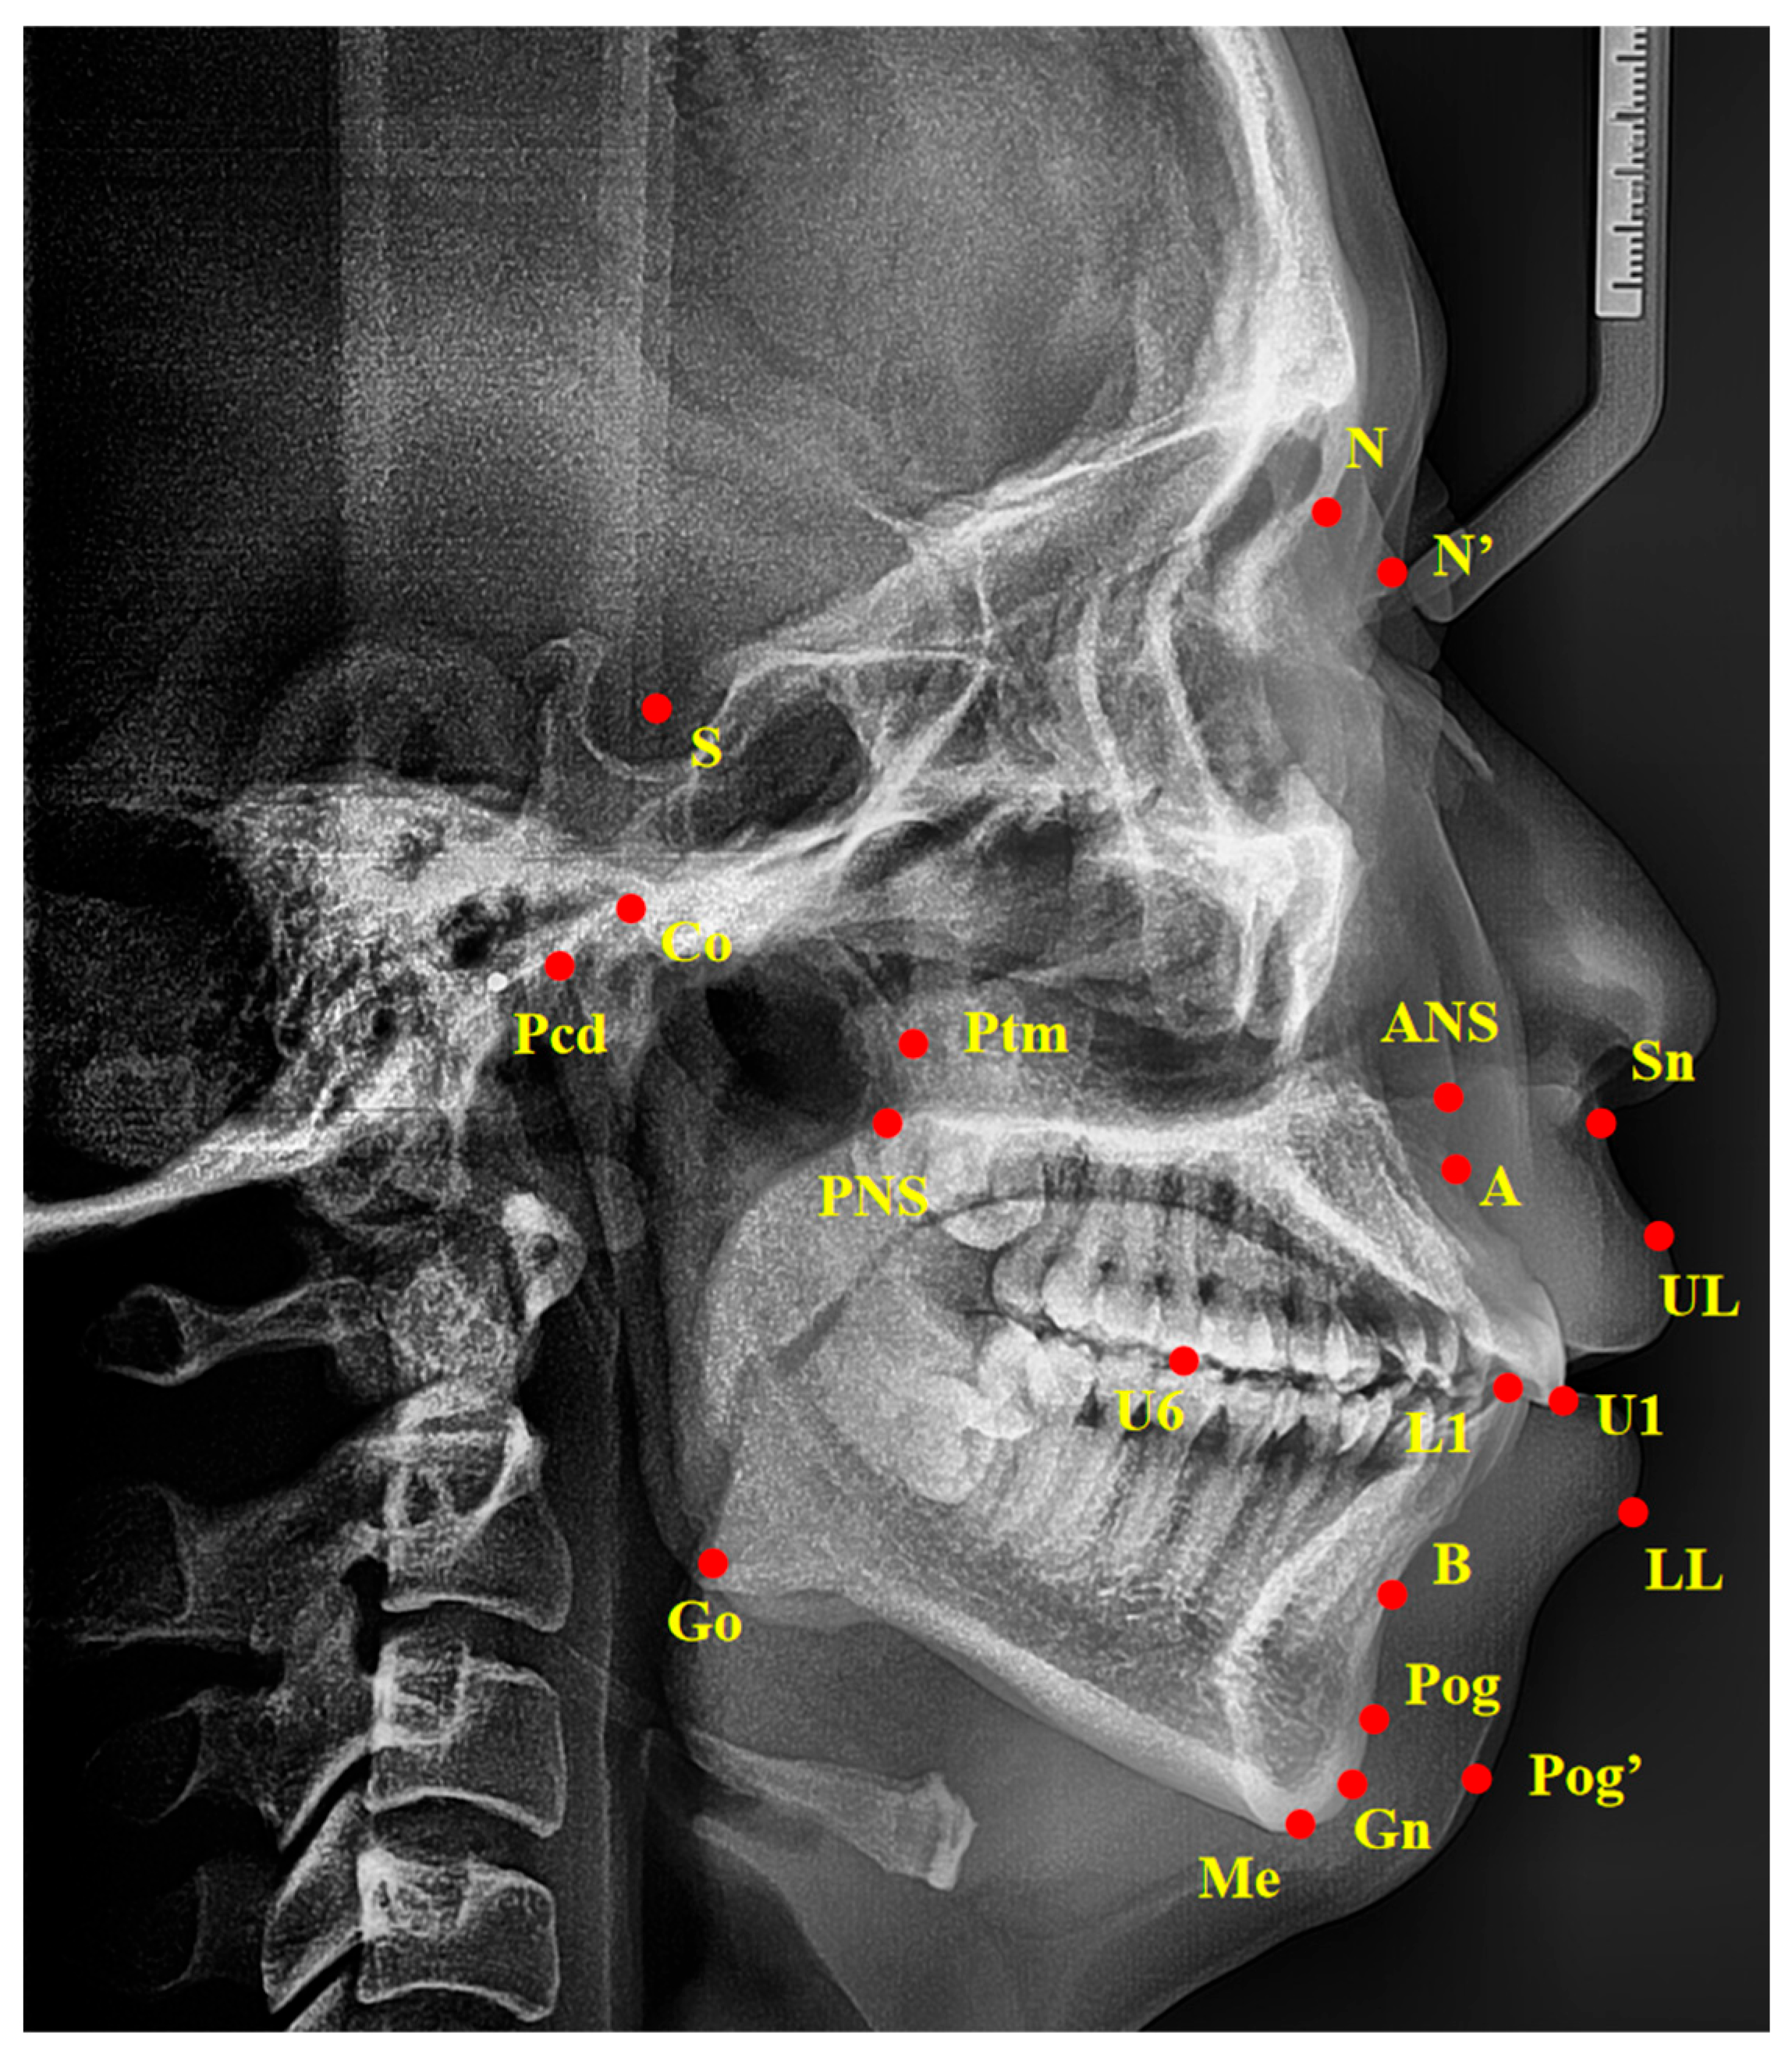

Standardized lateral cephalograms were taken with the same cephalostat at the Hospital of Stomatology, Sun Yat-sen University, with the patient in an upright position, with a natural head posture and centric occlusion. Cephalometric tracings were performed by an examiner blind to the PSG reports and clinical examination results, using the Digident software, version 2.10 (Boltzmann Zhibei Technology Co., Ltd., Chengdu, China) to calculate all angular and linear measurements [23]. All landmarks were automatically digitized and manually adjusted on each radiograph. Thirty-nine variables of linear and angular measurements were calculated from fourteen landmarks digitized on each radiograph as described in Figure 1 and Table 1. To evaluate the error of the method, 20 cephalograms were selected randomly and duplicate determinations were performed 4 weeks later by the same examiner. An intra-class correlation (ICC) coefficient was calculated to evaluate the intra-operator reliability. The values of all calculated intra-class correlation coefficients were greater than 0.95, showing repeated agreement with regard to all measurements.

Figure 1.

Landmarks of cephalometric analysis. Ba, basion; S, sella point; N, nasion; ANS, anterior nasal spine; PNS, posterior nasal spine; A, the deepest point in the concavity of the anterior maxilla between the anterior nasal spine and the alveolar crest; B, the deepest point in the concavity of the anterior mandible between the alveolar crest and pogonion; Pcd, the most posterosuperior point of the condylar head; Go, gonion; Gn, gnathion; Me, menton; Ptm, pterygomaxillary fissure point; Pog, pogonion; U1, upper incisors; L1, lower incisors; U6, the mesial buccal cusp of upper maxillary first molar; UL, upper lip; LL, lower lip; N’, nasion of soft tissue; Pog’, pogonion of soft tissue; Sn, subnasale.